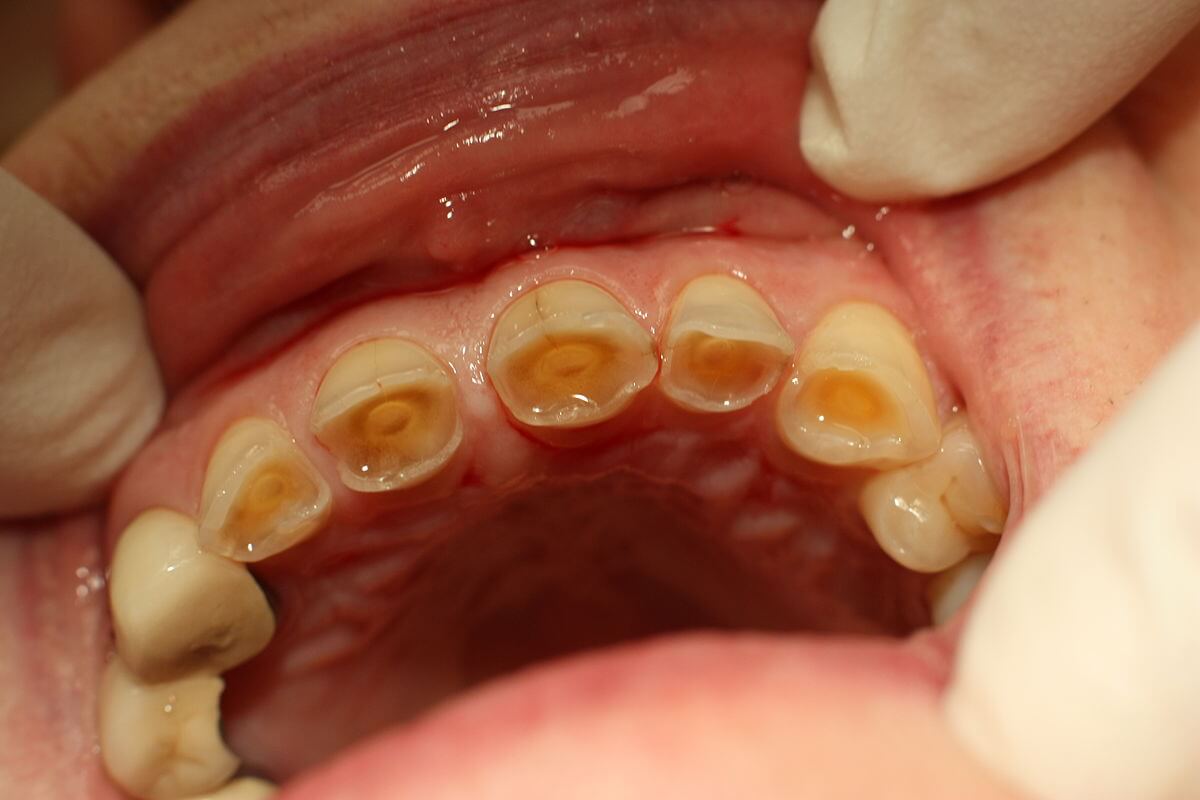

Can You Repair Ground Down Teeth?

Yes — ground down teeth can absolutely be repaired. Whether caused by teeth grinding (bruxism), acid erosion, or ageing, modern dentistry offers advanced techniques to restore worn teeth both cosmetically and functionally.

What Causes Teeth to Grind Down?

• Bruxism (Teeth Grinding): Often occurs at night or during stress

• Acid Erosion: From acidic foods/drinks or acid reflux

• Tooth Wear from Age or Use: Over time, enamel naturally wears

• Misaligned Bite: Can cause uneven pressure on certain teeth

Symptoms of Worn Down Teeth

• Short or flat-looking teeth

• Increased sensitivity to hot/cold foods

• Chips or cracks, especially on the front teeth

• Jaw pain or headaches (linked to clenching)

• Changes in your bite or smile appearance

How Can Dentists Repair Ground Down Teeth?